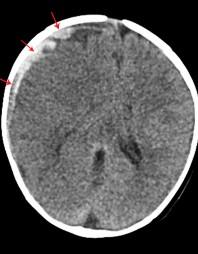

CT: Signs of Ischemic/Anoxic Injury

Loss of grey white juncture

White cerebellar sign

Pseudo Subarachnoid Hemorrhage Reversal of Basal Ganglia

Normal 2-year-old

8-yearold, encephalopa thy:

Reversal of Basal Ganglia density

Day 1 Admittance

Day 3, Progressive encephalopathy with seizures